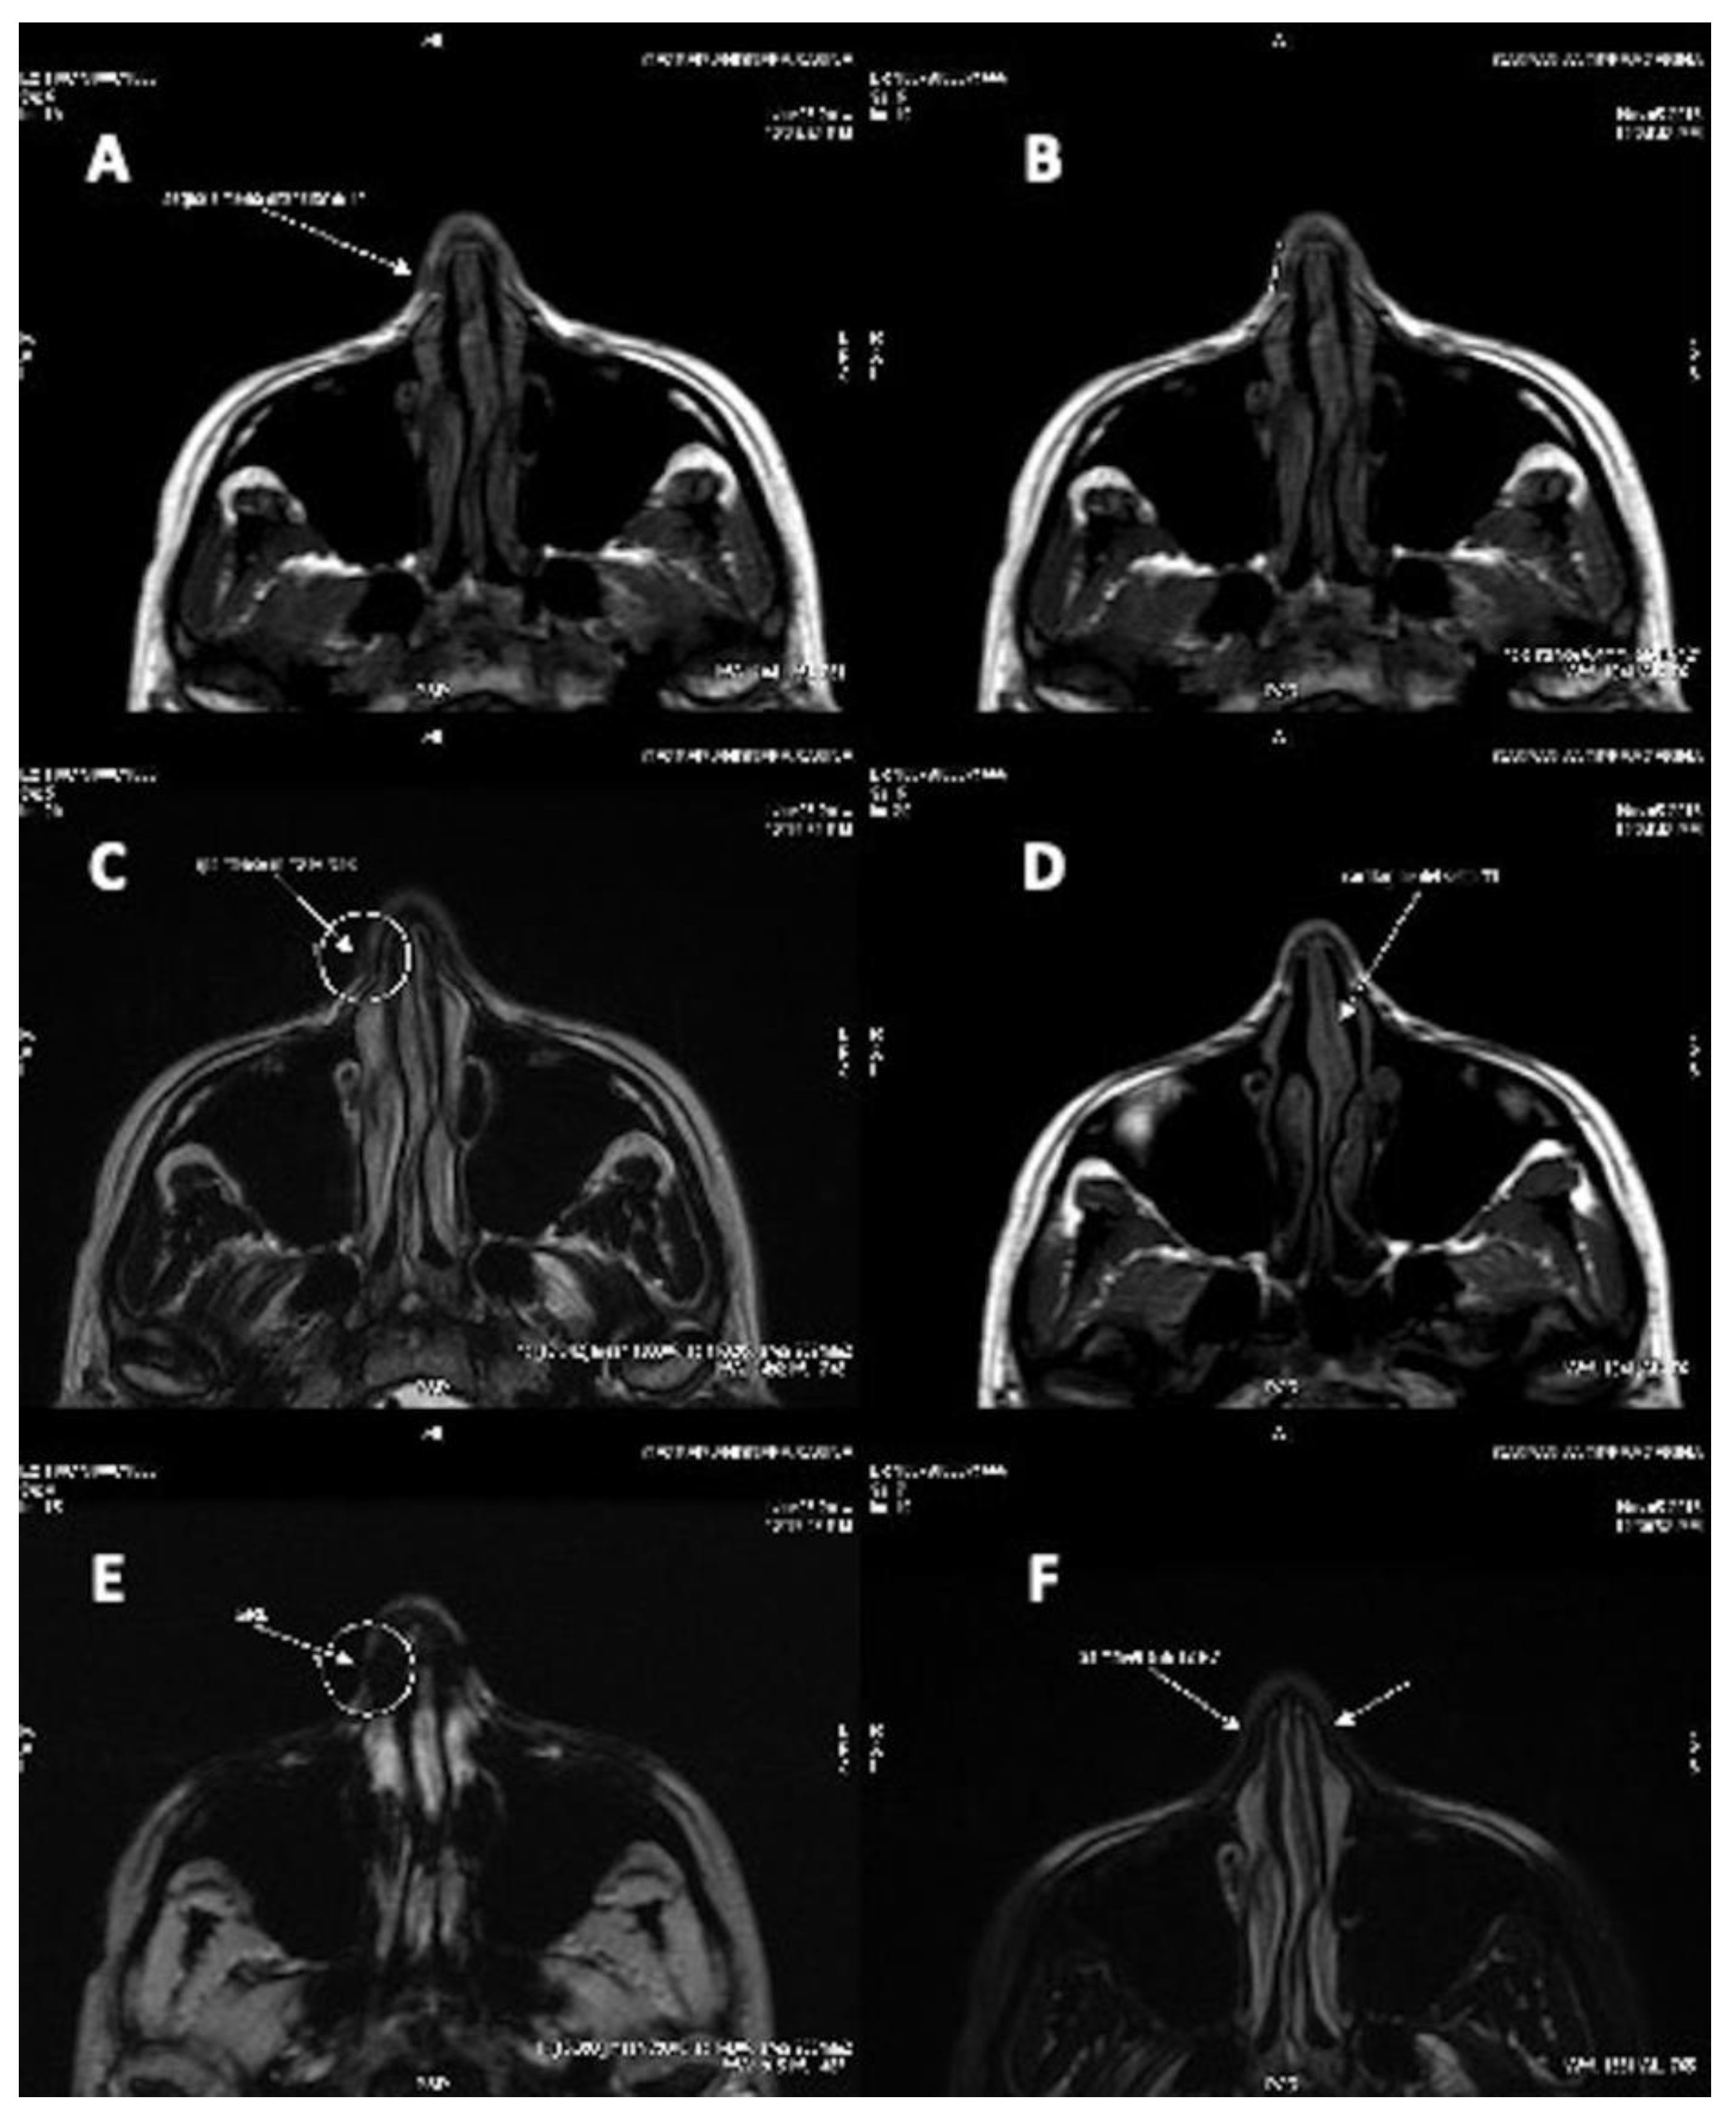

3.2. Clinical Long-Term Results and Instrumental Observation